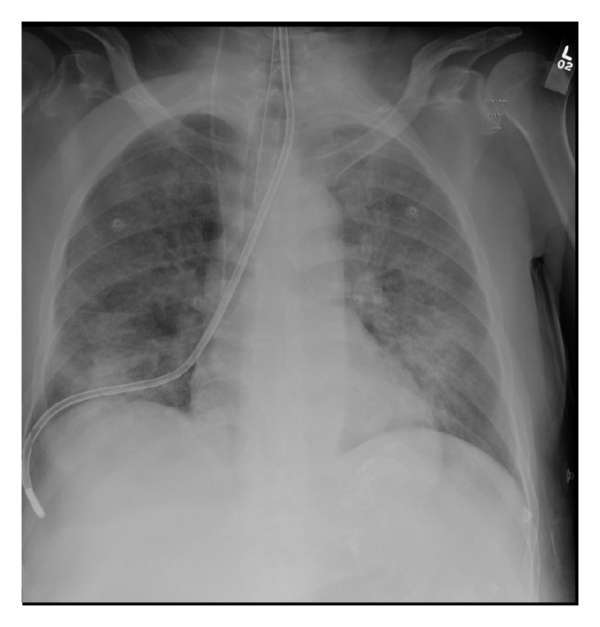

After NG tube insertion, chest X-ray showed misplaced NG tube at the right main bronchus down to the right pleural space and development of new 7.8 mm right sided pneumothorax (Figure 1, chest X-ray). The NG tube had been immediately removed and PEEP was decreased to 5 cmH2O. Over few minutes, the patient became progressively hypotensive and hypoxic, requiring higher doses of norepinephrine infusion and FiO2 of 60% to maintain 95% saturation. Right sided chest tube was inserted and the repeated X-ray revealed new subcutaneous emphysema (Figure 2). Using direct laryngoscopy technique, nasogastric tube was inserted under vision.